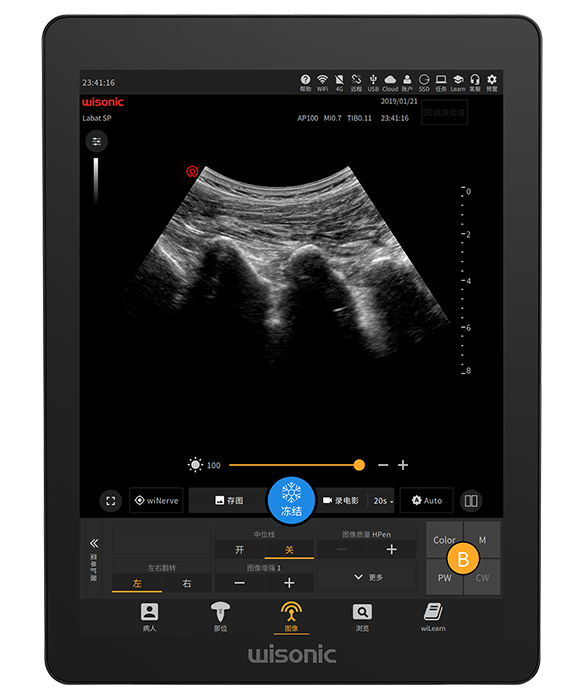

Le plus grand écran tactile complet de l'industrie21,3 pouces

Anti - éblouissement, pleine taille, haute sensibilité

Panneau de contrôle simplifié

Capteur d'empreintes digitales intégré et trackball fluide

Prise en charge de la désinfection liquide

Fonctionnement multi-touch

Panneau minimal pour la personnalisation clinique

Anti-éclaboussures

Trackball étanche haute sensibilité

Joystick multifonction

wiNerve

Reconnaissance intelligente des nerfs par IA

Reconnaissance en temps réel